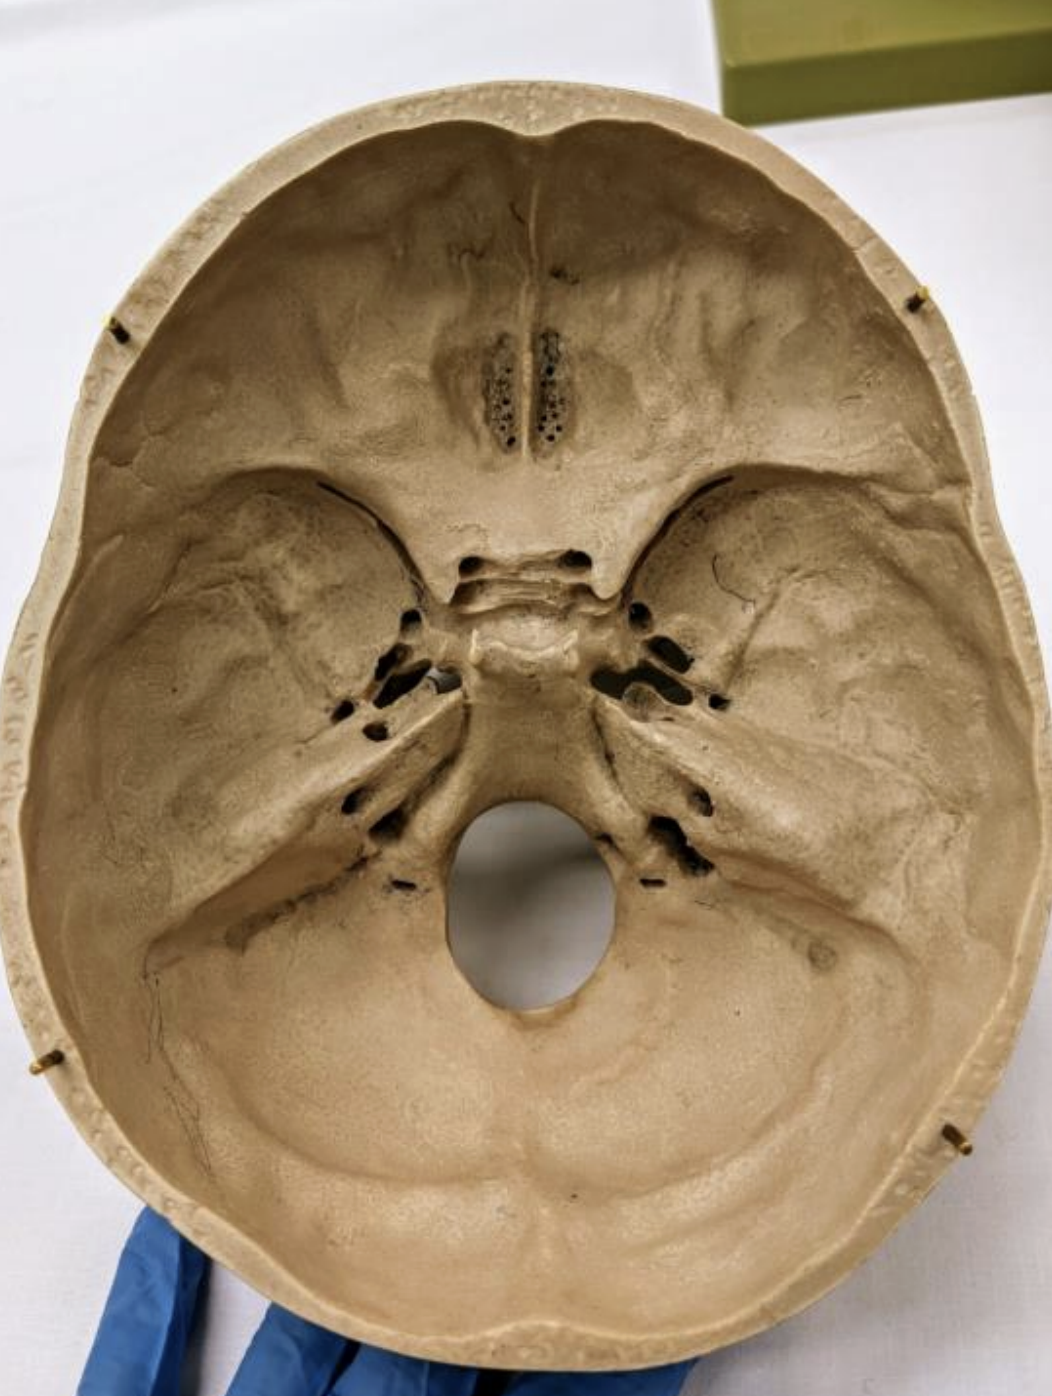

Orientations of brain

Flow of CSF

Cranial Dural Folds

Falx cerebri

Tentorium cerebelli

Falx cerebelli.

Circle of Willis

Superior sagittal sinus

Straight sinus

Confluence of sinuses

Transverse sinuses

Sigmoid sinuses

Cavernous sinuses

Intercavernous sinus

Superior petrosal sinuses/inferior petrosal sinuses

Occipital sinus

Sphenoparietal sinuses